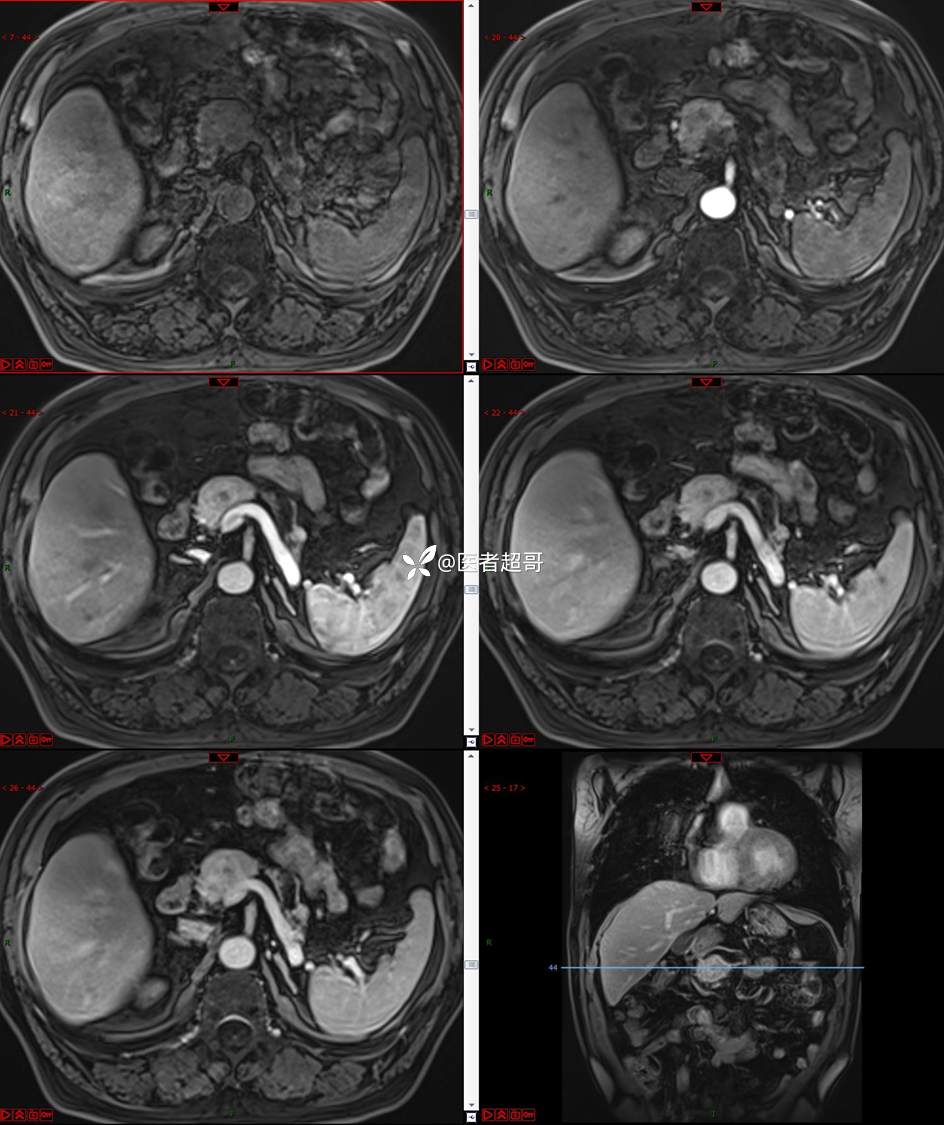

【影诊笔记677】查体发现胰腺占位性病变1周,细节决定成败,请诊断分析!

主 诉:查体发现胰腺占位性病变1周。

现病史:患者1周前在当地查体时发现胰腺占位性病变,无恶心、呕吐,无腹痛,无寒战、高热,无咳嗽、咳痰等异常不适,来我院门诊查上腹部CT平扫+强化:胰腺尾部异常密度灶。今为求进一步治疗,门诊以“胰腺占位性病变”收入院。患者自发病以来,一般情况可,神志清,精神可,普通饮食,二便正常,体重及体力无明显改变。